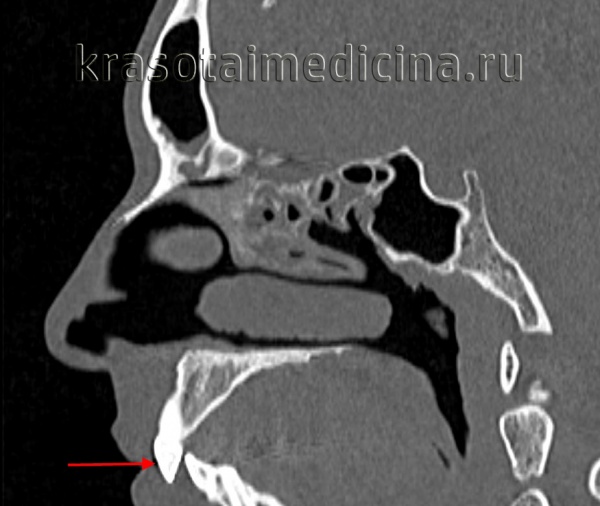

КТ черепа (3D-рендеринг). Прогнатический прикус, зубы верхней челюсти (красная стрелка) выстоят кпереди, отсутствует контакт резцовых краев при смыкании.

КТ черепа. Прогнатический прикус, зубы верхней челюсти (красная стрелка) выстоят кпереди (этот же пациент).

Дистальное положение челюстей на телерентгенограмме

- Компьютерная томография или 3D-проекция черепа. По ней можно оценить важные показатели для ортодонтического лечения: клиническую форму прикуса, размер и положение челюстей. Положение и соотношение зубов в костной ткани и ее объемы. Состояние и положение головки височно-нижнечелюстного сустава. Трехмерная модель черепа дает более точное представление о положении зубов и челюстей, чем классических 2D-снимок черепа в боковой проекции.